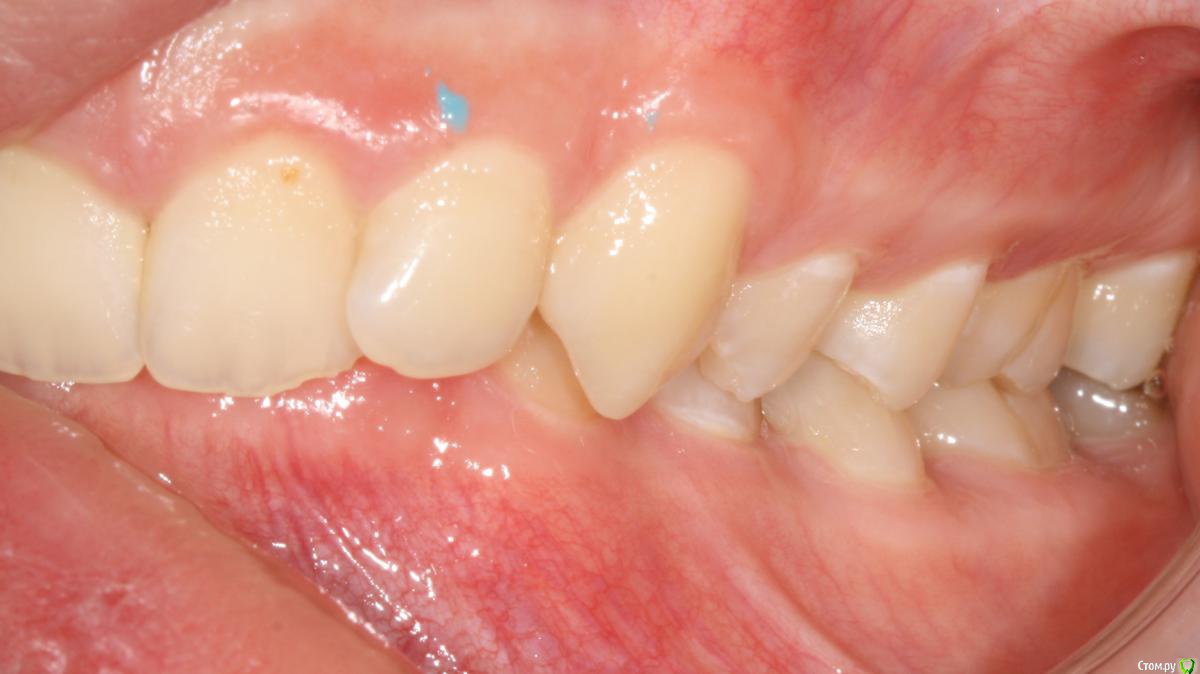

Opdihatop Опубликовано 24 октября, 2017 Поделиться Опубликовано 24 октября, 2017 И еще раз здравствуйте! Сразу хочу презентовать еще одного мальчика. Лично я такого еще не видел, а потому хочу понять, что тут делать. Думаю, невооруженным взглядом видно гипертонус и гиперплазию массетеров и гиперплазию углов н/ч из-за этого. Из-за чего это может быть и что тут делать? Как расслабить и что вообще делать с мышцами? Слать ли на сцинтиграфию (мало ли, может рост продолжается)? Есть ли шанс повысить прикус или такие мышцы все равно вколотят? Члх или нет? Заранее спасибо! Ссылка на комментарий

krokomot Опубликовано 24 октября, 2017 Поделиться Опубликовано 24 октября, 2017 Ботокс хорошо расслабляет, в данной ситуации, следует дифференцировать от остеодисплазии, херувизма. 1 Ссылка на комментарий

Brigita Опубликовано 25 октября, 2017 Поделиться Опубликовано 25 октября, 2017 (изменено) дифференцировать от остеодисплазии, херувизма.точно не херувизм. там в полости рта другая картина совсем, а по поводу дисплазии - она чаще односторонняя, может быть.... Изменено 25 октября, 2017 пользователем Brigita Ссылка на комментарий

krokomot Опубликовано 25 октября, 2017 Поделиться Опубликовано 25 октября, 2017 Выкладывайте кт, сильно сомневаюсь что повышенный тонус массетер привел к гиперплазии углов. Перестройка да, гиперплазия нет. Ссылка на комментарий